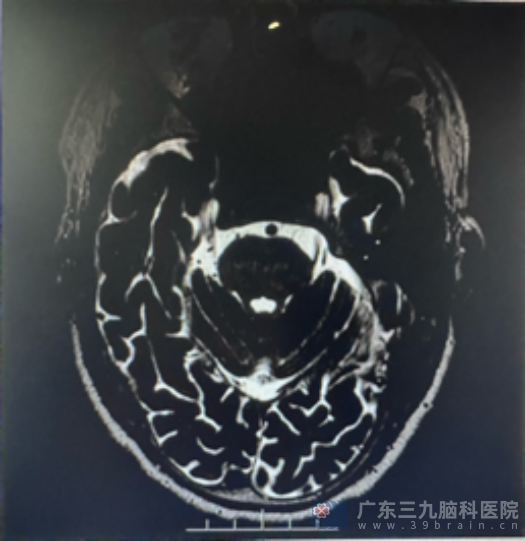

手术中,医生通过高清显微镜放大下的精细操作,先找到“责任血管”,再小心轻柔地在血管和神经之间放置特殊的隔离材料,解除血管对三叉神经的压迫。这个过程如同“在发丝间跳舞”,需要极高的精准度,既要有效隔离血管,又要保护好周围的重要神经和血管结构。